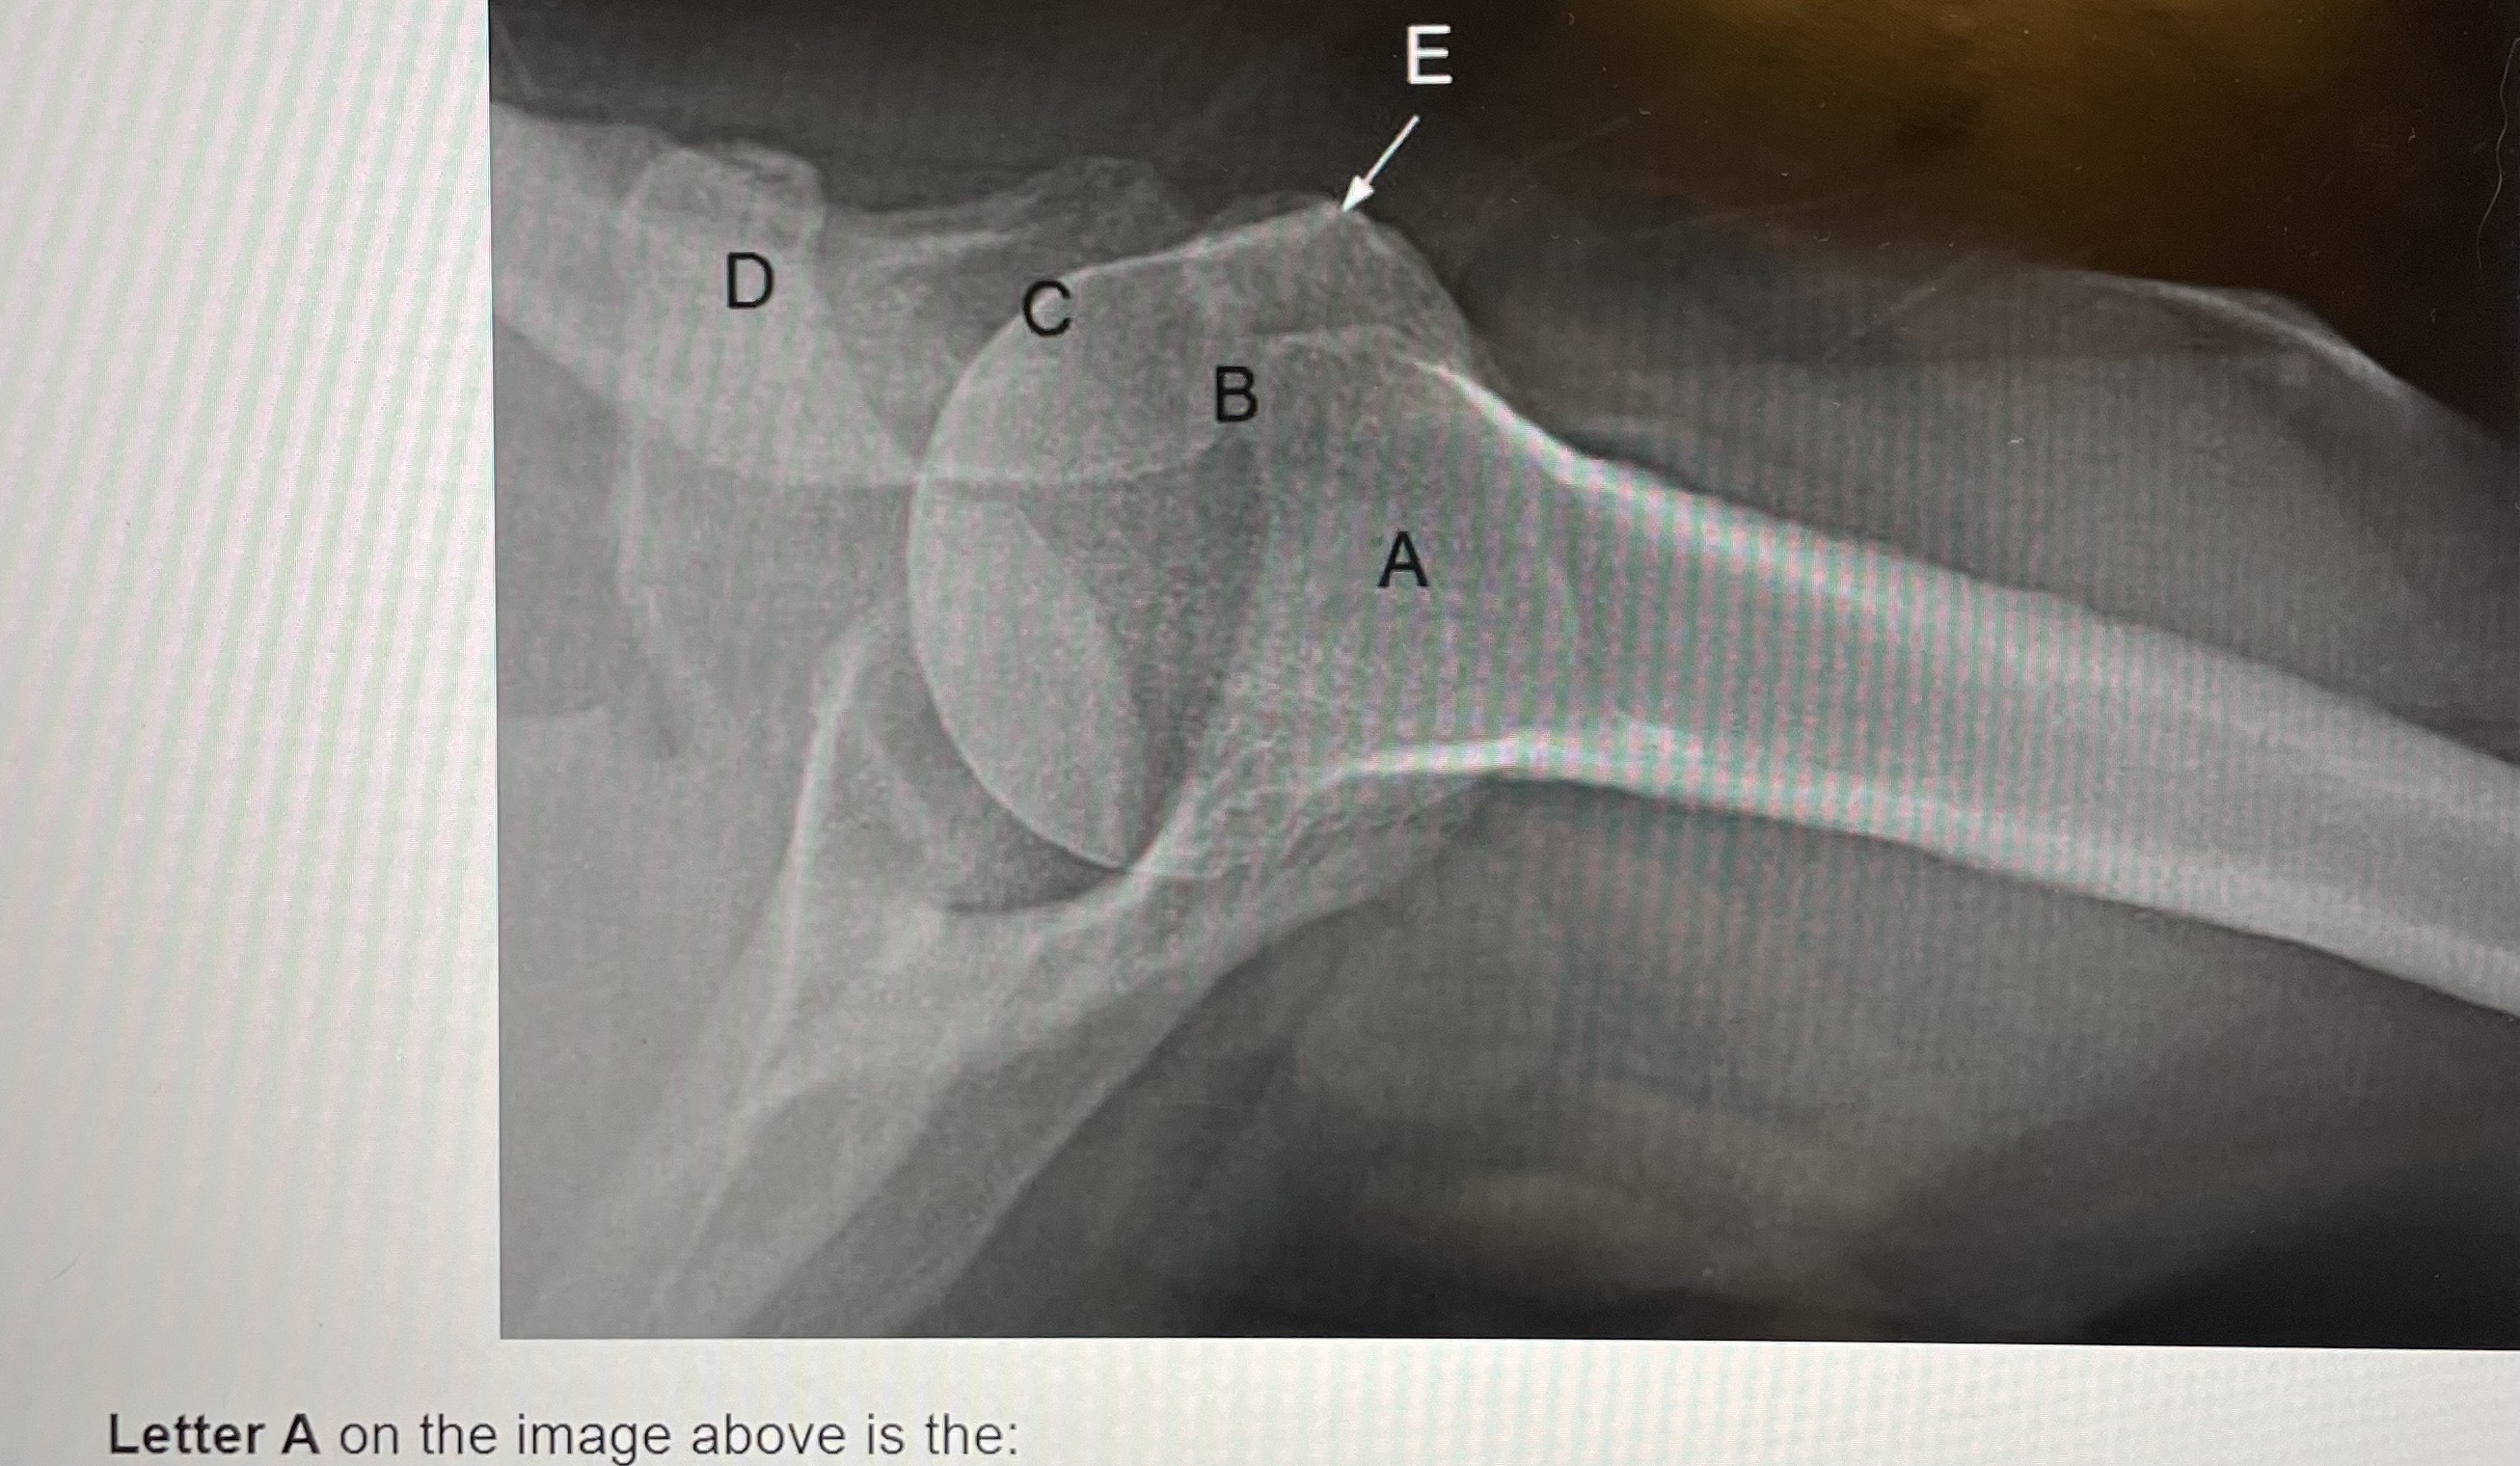

what is C?

manubrium

what is E?

body, corpus, gladiolus